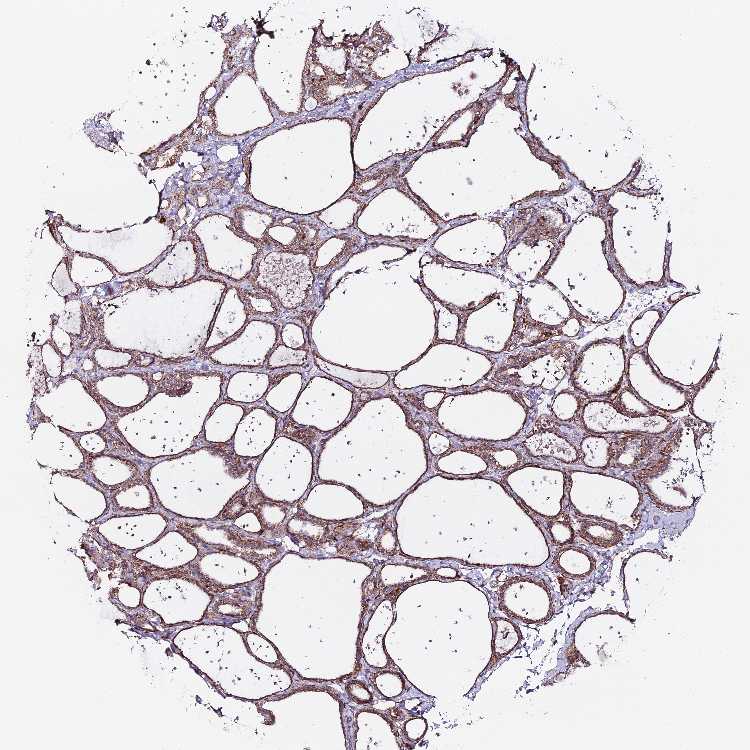

Antibody staining in the annotated cell types in the current human tissue is reported as not detected, low, medium, or high. This score is based on the staining intensity and fraction of stained cells.

Information about each individual sample is listed below, including gender, age, a tissue section image and estimated fractions of cell types. pTPM (transcripts per million) values give a quantification of the gene abundance which is comparable between different genes and samples.

Female, age 55

Thyroid gland sample 250 pTPM: 0